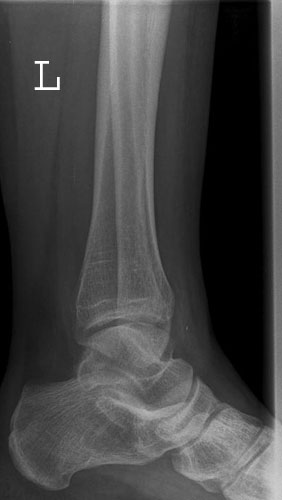

OSG a.p.

Außenrotation bzw ungenügende Rotation des Fußes nach innen. Der mediale Gelenkspalt projiziert sich besonders schön frei, hingegegen ist der laterale Spalt verschattet.

Fuß weiter nach innen drehen lassen, bis beide Malleolen auf einer Höhe parallel zum Film stehen.